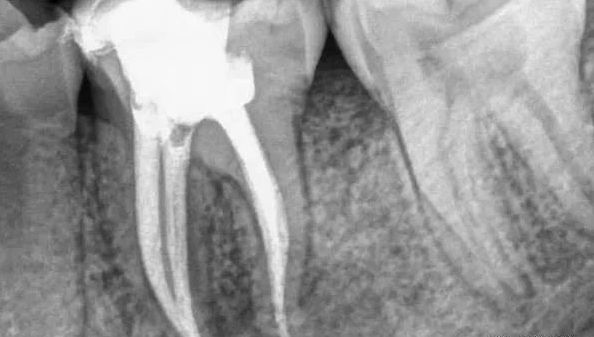

“根管治疗”不仅仅是要将“根管”中的牙髓“杀死”,还要将牙髓从“根管”中清除出来,然后要进行彻底清理和严格消毒,并用人工的充填材料将“根管”严密填塞。

我们的后磨牙在正常咀嚼时可能会承受到五十至七十公斤的力量。根管治疗之后的牙齿变得脆弱,在使用中随时面临劈裂的危险,所以,根管治疗之后的牙齿应该需要保护起来。

当牙齿做完根管治疗,由于牙齿自身的结构及治疗的需要,牙冠中心一般都是空的,这时,如果直接做牙套,其抗折断力很差,一般都需要在牙根上打上桩钉,做出个结实的核,以对抗牙齿使用中的折断力。

对于后牙来说,做完根管治疗之后一定要做上牙冠,否则在承受咬合力量时,牙齿容易出现断裂。少数做完根管治疗的后牙,若是要做单一的牙冠,只需将所剩牙质修补足够,则可不需做桩钉,但若做完根管治疗的后牙是要作为假牙的基牙,则无论牙质所剩多少,最后都能做好桩钉。